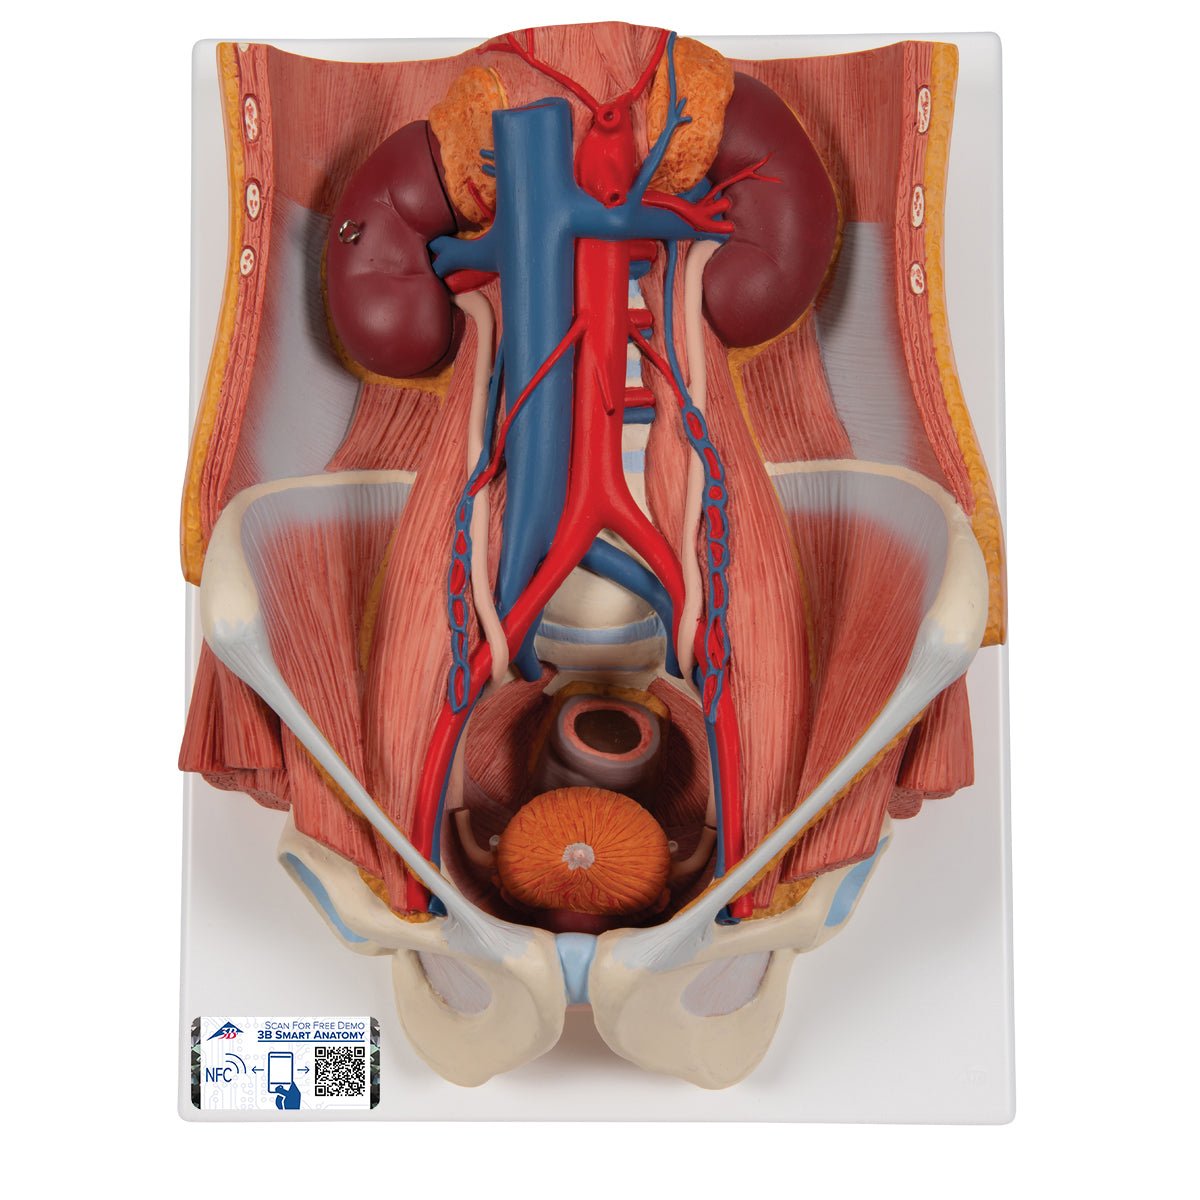

Amazon.co.jp: 機能解剖学 functional anatomy[理学療法 ME316。Amazon.co.jp: 機能解剖学 functional anatomy[理学療法 ME316。Dual Gender Urinary System, 6-part – GTSimulators.com。

機能解剖学(functionalanatomy)は、解剖学を基礎とした身体運動に関する学問であり、疾患や障がいの種類を問わないリハビリテーション分野の専門基礎知識になります。

本作は、大きく「上肢」「下肢」「頭頸部・体幹」の3つに分類し、各体節に細分化して構成しています。

また、骨格模型画像、解剖図を中心に、動画、イラストを用いながら詳しく解説しています。

機能解剖学(functionalanatomy)は、解剖学を基礎とした身体運動に関する学問であり、疾患や障がいの種類を問わないリハビリテーション分野の専門基礎知識になります。

本作は、大きく「上肢」「下肢」「頭頸部・体幹」の3つに分類し、各体節に細分化して構成しています。

また、骨格模型画像、解剖図を中心に、動画、イラストを用いながら詳しく解説しています。